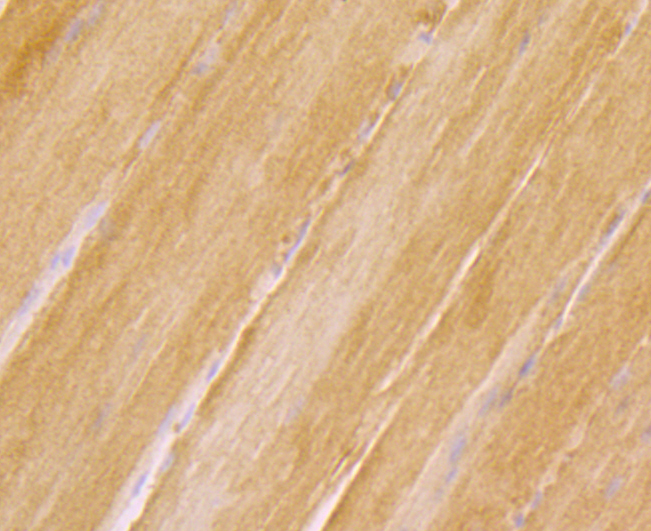

Immunohistochemical analysis of paraffin-embedded rat skeletal muscle tissue using anti-RYR2 antibody. Counter stained with hematoxylin.

Immunohistochemical analysis of paraffin-embedded human fetal skeletal muscle tissue using anti-RYR2 antibody. Counter stained with hematoxylin.